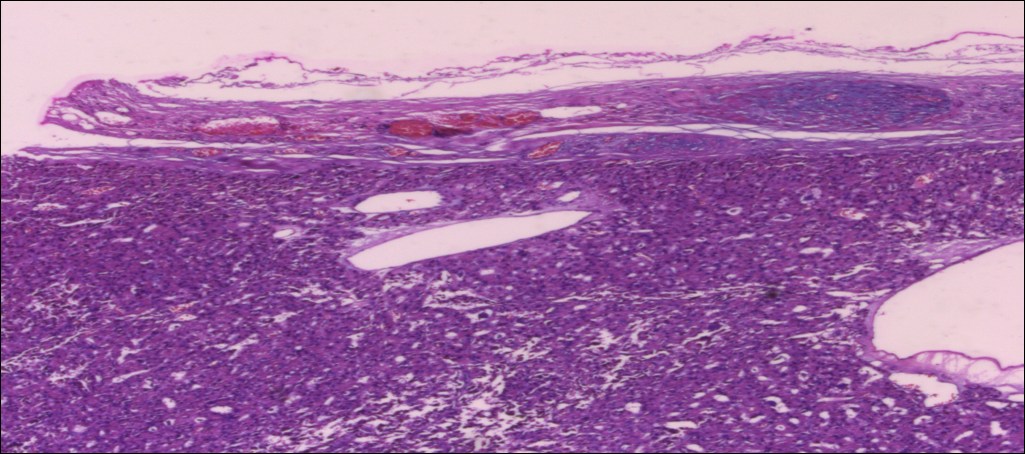

甲状腺嗜酸性细胞腺瘤

性别

女

年龄

71岁

临床诊断

肿物待查

一般病史

发现甲状腺肿物5个月

标本名称

甲状腺右叶及峡部肿物

大体所见

(甲状腺右叶及峡部):暗褐结节,直径6cm,包膜完整

肿物包膜完整,镜下未见明确包膜、脉管侵犯

图1